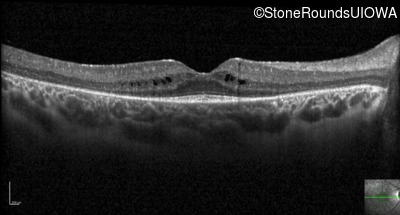

Optical Coherence Tomography - Right - 20/40

Exemplar / OCT Stack